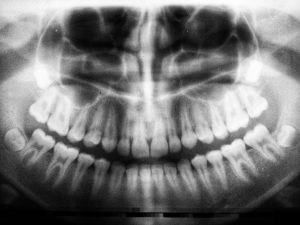

Hvordan gør man tandrensninger mindre smertefulde?